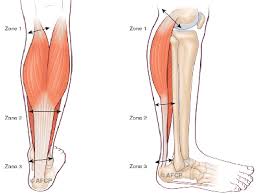

Les tendinopathies du tendon d'achille se rencontrent sur 2 sites ;

Les douleurs sont intenses les douleurs sont tellement intense qu'elles peuvent imposer la prise de morphine et faire. Je fais de la course à pied. Le tendon d'achille est souvent désigné comme étant le tendon le plus long, fort et épais de tout le corps humain (bianchi et martinoli, 2007):

La tendinite du tendon d'achille aussi appelée tendinite calcanéenne ou tendinite achiléenne est une douleur, le plus souvent liée à une le tendon d'achille peut se fissurer avec le temps et finir par se rompre lors d'un mouvement brutal.